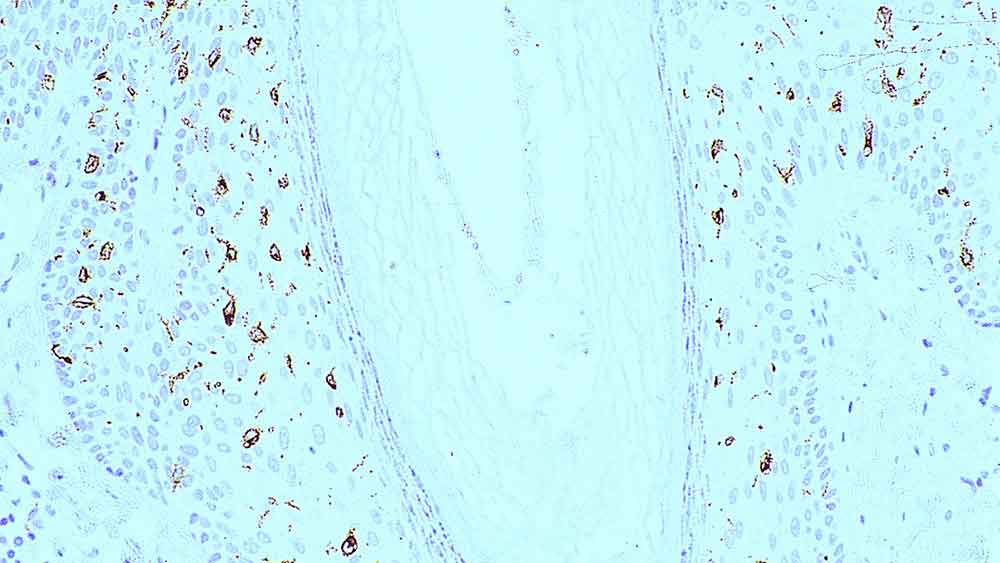

Human skin: immunohistochemical staining for langerin. Langerin: clone 12D6

La langérine est une lectine de type C transmembranaire de type II, possédant une spécificité de liaison du mannose. C'est une protéine de 40 kD uniquement présente dans les cellules de Langerhans, qui participe à l'internalisation des matériaux de la surface cellulaire de ces cellules dendritiques immatures.